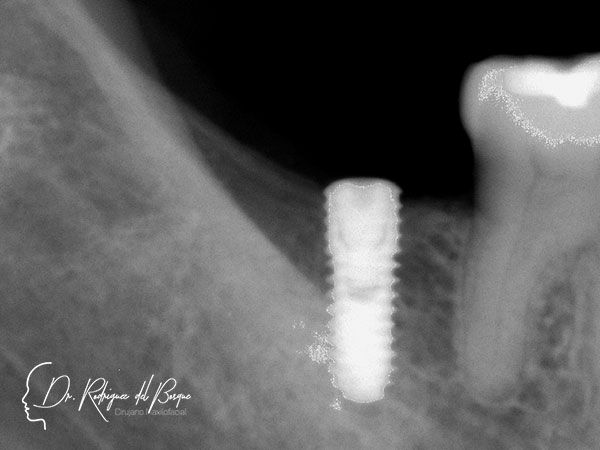

Implantes Dentales

Los implantes dentales están indicados cuando se ha perdido un organo dental, es una excelente opcion de tratamiento siempre y cuando se cumplan con los requisitos biológicos y protesicos para que un paciente Sea candidato.